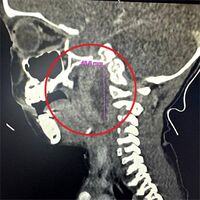

В больницу пациент поступил с выраженным отеком шеи и температурой до 39°C. Родители мальчика рассказали, что ребенок уже неделю болел ОРВИ. Они лечили его жаропонижающими самостоятельно, но это эффекта не давало. Медики провели обследование и установили, что у ребенка развился гнойный абсцесс в шее как осложнение перенесенной инфекции.

«Гнойный абсцесс в области шеи очень опасен, так как может привести к сужению дыхательных путей, повреждению сосудов и нервов, тромбообразованию и даже параличу», — рассказала заведующая оториноларингологическим отделением Елена Ковалец.

Мальчика доставили в ЛОР-отделение, где провели ему экстренную операцию по удалению гноя.